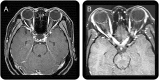

Figure 2. MRI lesions characteristic of MS

(A) Contrasting MS periventricular and callosal lesions, which are discrete, ovoid, and perpendicular to the ventricles. (B) Contrasting MS enhancing lesions, which are ovoid or open-ring gadolinium-enhanced lesions with well-defined borders. MS = multiple sclerosis.